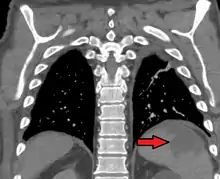

| Splenic infarct seen on CT | |

An abdominal CT scan is the most commonly used modality to confirm the diagnosis,[3] although abdominal ultrasound can also contribute.[4][5][6]